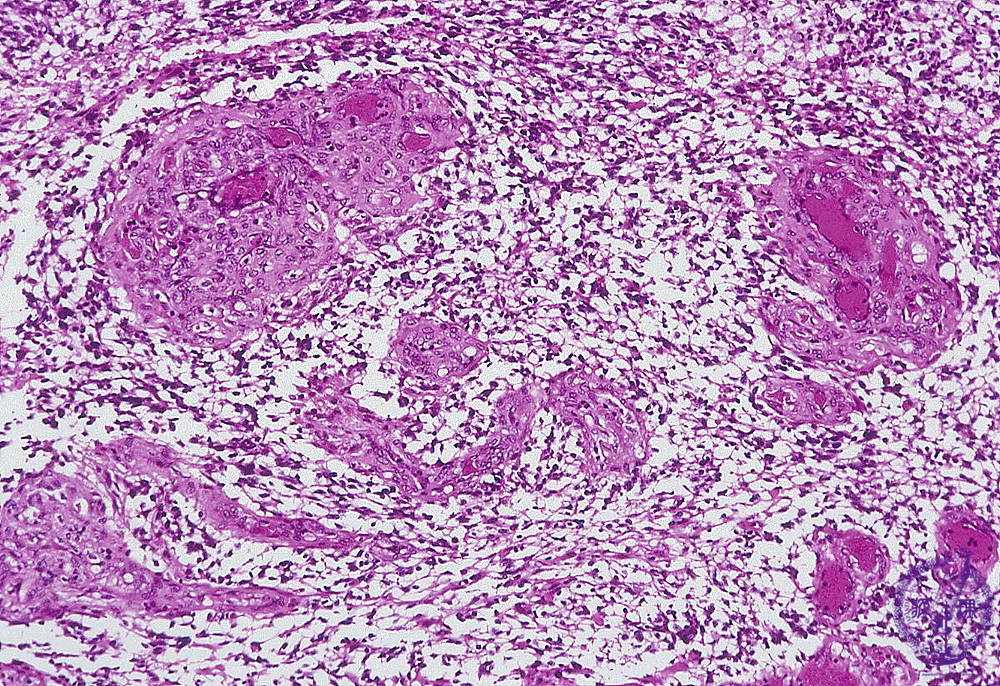

- ★(8)Glioma(Glioblastoma)

Microscopic findings (H.E. middle magnification): There were increased number of vessels with anintravascular proliferation of endothelial cells and thickening of the vascular wall (arrows). Sometimes, several vascular lumina were detected in a single vessel, also termed ‘glomeruloid structure’.